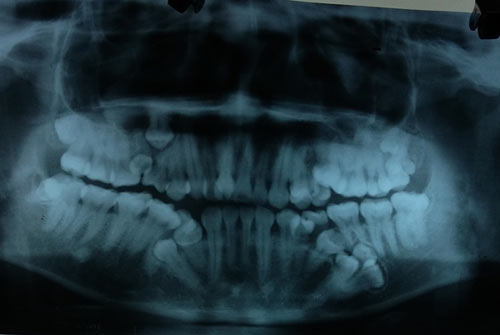

Hình ảnh chụp phim cho thấy bệnh nhân mọc thừa răng chi chít

Tại đây các bác sĩ đã hết sức bất ngờ khi phát hiện ngoài chiếc răng sâu, bệnh nhân bị mọc thừa đến 13 chiếc răng ở vị trí răng 4 và 5 trên 2 hàm. Các răng mọc lệch, chen chúc, dàn hàng ngang khiến việc vệ sinh khó khăn, gây sâu, viêm tủy.

BS Nguyễn Thanh Thái, Trưởng khoa Phẫu thuật Tạo hình Hàm mặt cho biết, sau khi chỉ định chụp CT, các bác sĩ lại tiếp tục phát hiện thêm bệnh nhân có 4 mầm răng chưa mọc. Hiện bệnh nhân đã được điều trị tủy dứt cơn đau răng, đồng thời làm xét nghiệm để chuẩn bị mổ bỏ các răng thừa vào tuần tới.